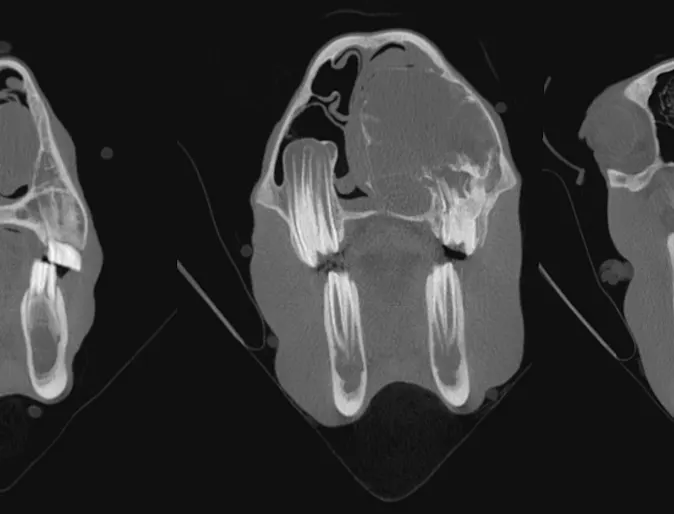

Aneurysmal Bone Cyst

9-month-old Percheron gelding presented for respiratory noise of 3 months duration. Final diagnosis on autopsy was Multilocular aneurysmal bone cyst.